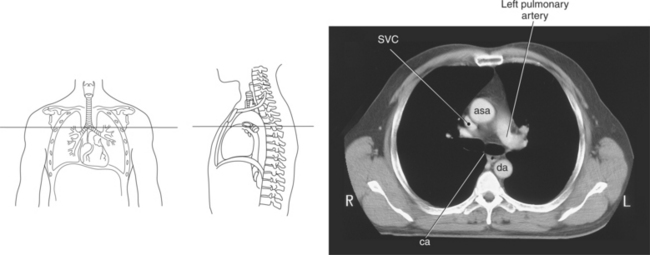

Figure 6.59 Axial CT scan of chest with ascending and descending aorta.

Key: SVC, Superior vena cava; asa, ascending aorta; da, descending aorta; ca, carina;

Blood travels to and from the heart through the great vessels, which include the aorta, pulmonary arteries and veins, and superior and inferior venae cavae (Figures 6.54 and 6.55). The aorta is the largest artery of the body and can be divided into the ascending aorta, aortic arch, and descending aorta. The ascending aorta begins at the base of the left ventricle at the level of the sternal angle, then curves superiorly and posteriorly as the aortic arch over the root of the left lung. The top of the aortic arch is approximately at T3 (Figures 6.56 and 6.57). The arch continues as the descending aorta posterior to the left bronchus and pulmonary trunk, on the left side of the vertebral body of T4 (Figures 6.58 and 6.59). The descending aorta passes slightly anterior and to the left of the vertebral column as it descends through the thoracic and abdominal cavities (Figure 6.60). While in the thoracic cavity, the descending aorta is commonly called the thoracic aorta, and while in the abdominal cavity, it is called the abdominal aorta. The pulmonary trunk is the origin of the right and left pulmonary arteries and lies entirely within the pericardial sac. It arises from the right ventricle and ascends in front of the ascending aorta, courses posteriorly and to the left, where it bifurcates at the level of the sternal angle (T4) into the right and left pulmonary arteries (Figures 6.61 through 6.63). The pulmonary trunk is attached to the aortic arch by a fibrous cord called the ligamentum arteriosum, the remnant of an important fetal blood vessel (ductus arteriosus) that links the pulmonary and systemic circuits during fetal development (Figures 6.54 and 6.61). The right pulmonary artery courses laterally, posterior to the ascending aorta and superior vena cava, and anterior to the esophagus and right mainstem bronchus, to the hilum of the right lung. At the root of the right lung, the right pulmonary artery divides into two branches, with the lower branch supplying the middle and inferior lobes and the upper branch supplying the superior lobe (Figures 6.61 through 6.64). The left pulmonary artery, shorter and smaller than the right, is also the most superior of the pulmonary vessels. It travels horizontally, arching over the left mainstem bronchus, and enters the hilum of the left lung just superior to the left mainstem bronchus (Figures 6.61 through 6.64). Within the lungs, each pulmonary artery descends posterolateral to the main bronchus and divides into lobar and segmental arteries, continuing to branch out and to follow along with the smallest divisions of the bronchial tree (Figures 6.61 and 6.64). Located inferior to the pulmonary arteries are the four pulmonary veins, two each (superior and inferior) extending from each lung to enter the left atrium (Figures 6.54, 6.55, 6.61, and 6.64 through 6.68). They commence in a capillary network along the walls of the alveoli, where they are continuous with the capillaries of the pulmonary arteries. The venous capillaries merge to form small vessels that unite successively to eventually form a single trunk for each lobe: three for the right and two for the left lung. Frequently the trunk from the middle lobe of the right lung unites with the trunk from the upper lobe, forming just two trunks on the right side prior to entering the left atrium. The right superior pulmonary vein collects blood from the upper lobe segments of the right lung and passes anterior and inferior to the right pulmonary artery, behind the superior vena cava. The right inferior pulmonary vein receives blood from the right lower lobes of the lung and crosses behind the right atrium to the left atrium (Figures 6.61 and 6.69 through 6.71). The left superior pulmonary vein receives blood from the left upper lobe of the left lung and courses anterior and inferior to the left main bronchus as it enters the left atrium. The left inferior pulmonary vein drains the inferior lobe of the left lung and passes toward the left atrium anterior to the bronchi (Figures 6.61 and 6.72 through 6.74). The pulmonary veins course more horizontally than the pulmonary arteries and are ultimately oriented toward the left atrium. At the root of the lungs, the pulmonary veins are anterior to the pulmonary arteries, which are anterior to the bronchus. While within the lungs, the branches of the pulmonary arteries are anterior to the bronchi, which are anterior to the pulmonary veins. The superior and inferior venae cavae are the largest veins of the body. The superior vena cava is formed by the junction of the brachiocephalic veins, posterior to the right first costal cartilage, and carries blood from the thorax, upper limbs, head, and neck (Figure 6.24). As it travels inferiorly, it is located posterior and lateral to the ascending aorta before entering the upper portion of the right atrium (Figures 6.54 through 6.59). The inferior vena cava is formed by the junction of the common iliac veins in the pelvis and ascends the abdomen to the right of the abdominal aorta and anterior to the vertebral column. It passes through the caval hiatus of the diaphragm and almost immediately enters the inferior portion of the right atrium (Figures 6.75 and 6.76).